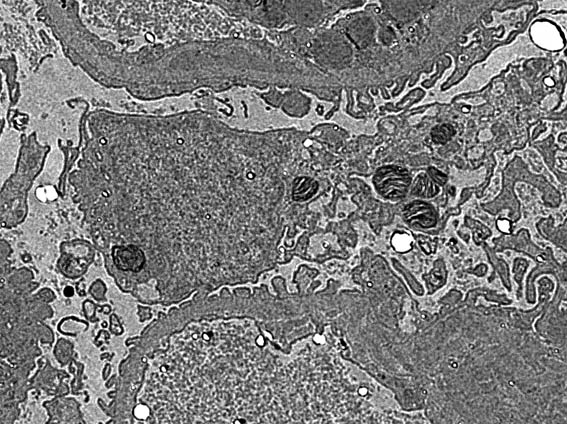

Figura 7. ME, aumento original: X4.000.